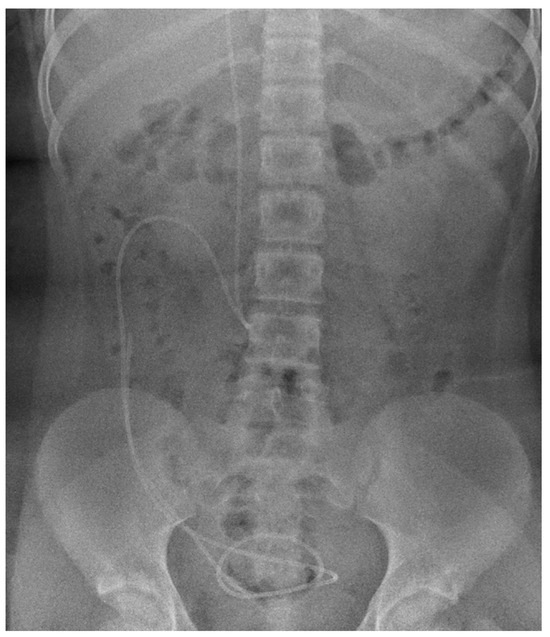

| Type of Atrophy | |||

|---|---|---|---|

| Primary | Secondary | Focal | |

| Mechanism | Primary abnormality of myelination | Diffuse injury | Focal injury |

| Causes | Hypomyelinating leukoencephalopathies, Metabolic disorders affecting white matter, Microcephaly | Hypoxic–ischemic encephalopathy, HIV-induced encephalopathy, Hydrocephalus, Demyelinating diseases | Dysgenesis of corpus callosum, Localized metabolic disturbances, Hypoglycaemia, Prematurity-related injury of white matter, HIV-related atrophy, Brain infarction and vasculitis, Traumatic brain injury |